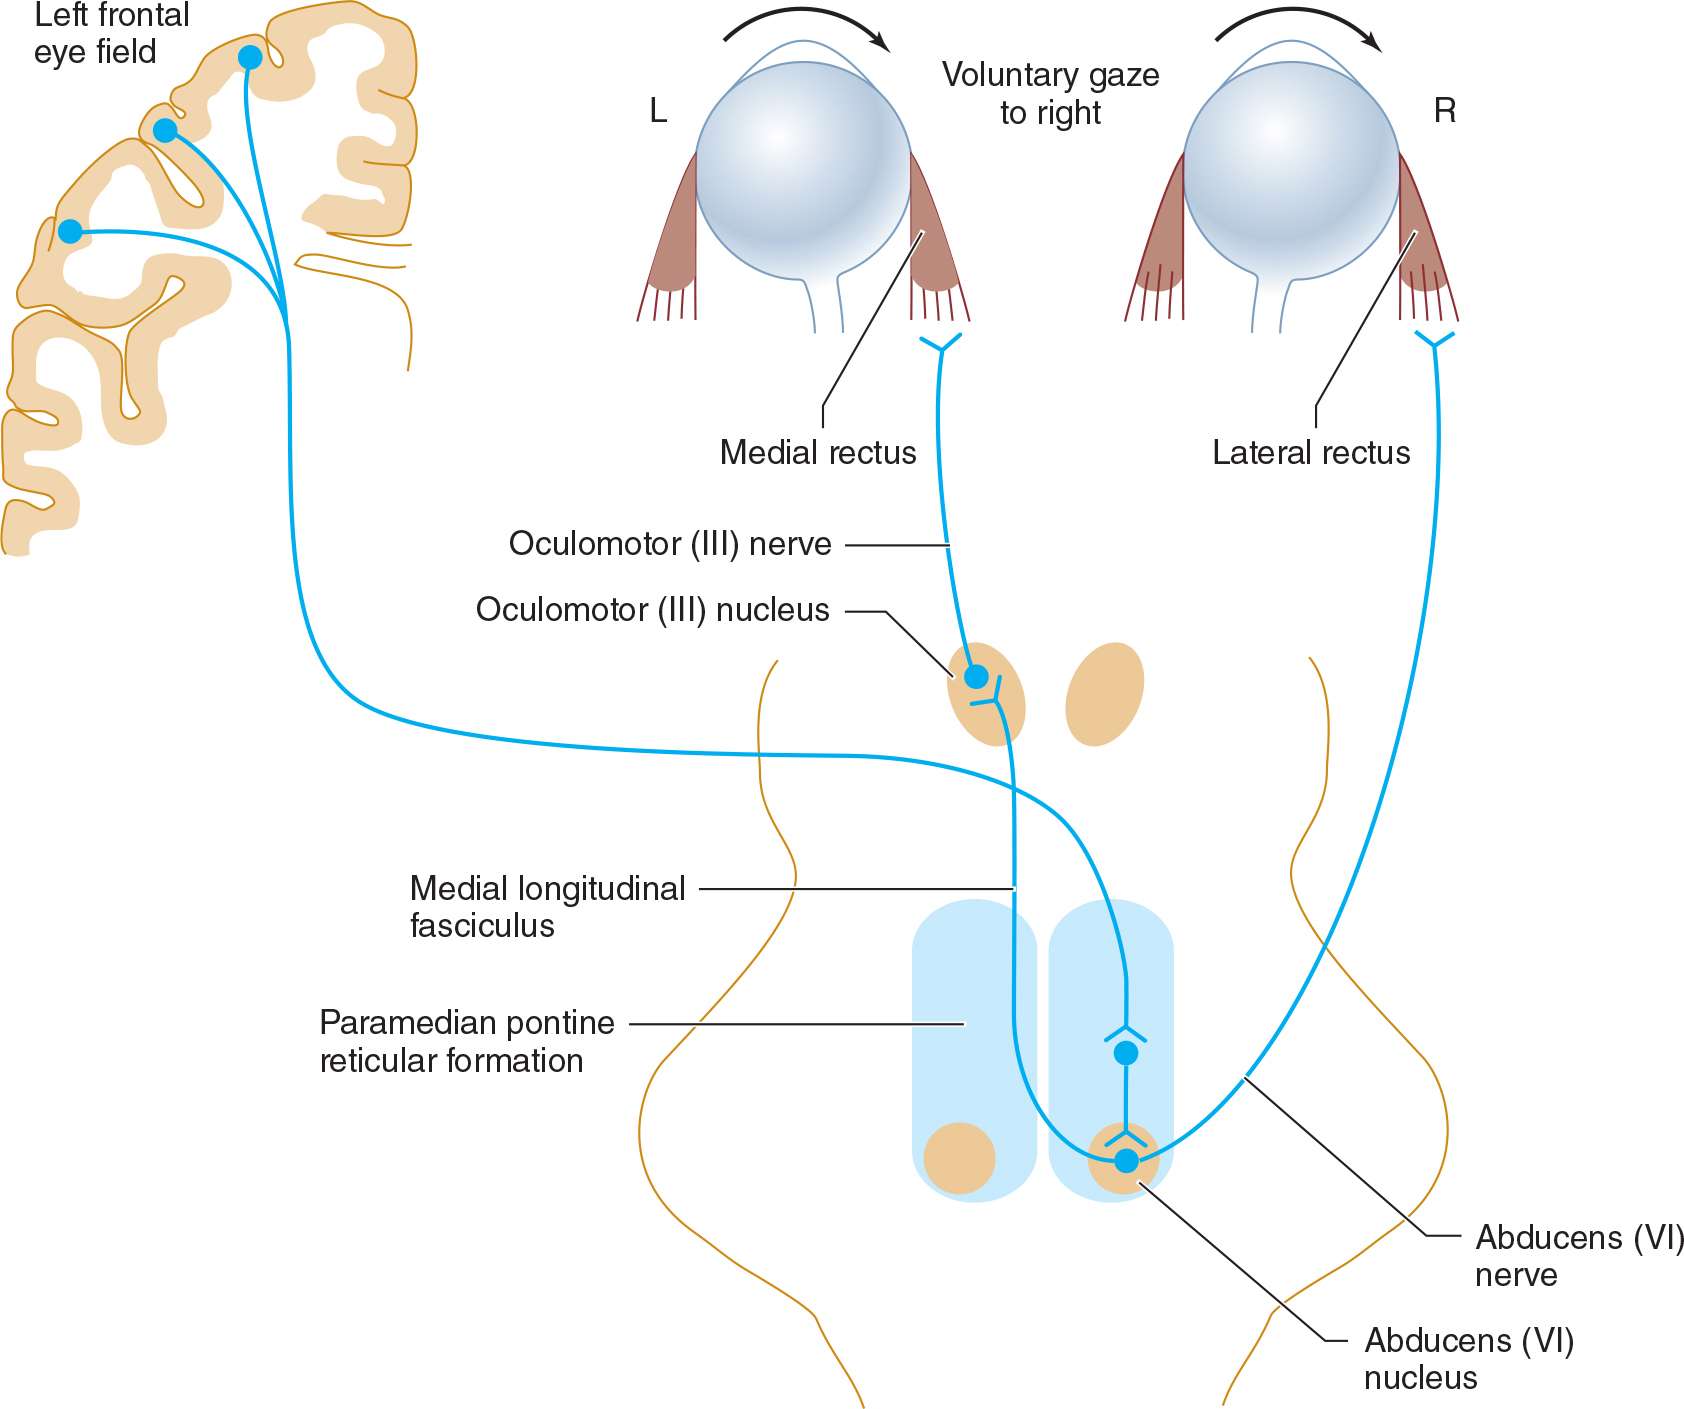

MSE: مختلبیمار آقای ۶۲ ساله MR با شکایت تشدید ضعف اندام تحتانی و اختلال تکلم و اختلال در Horizontal gaze چشم راست به این مرکز مراجعه کرده است . فورس اندام های فوقانی 5/5 و فورس اندام های تحتانی 4/5 است ، بیمار در چشم راست اختلال در adduction حین حرکت هر دو چشم دارد اما در convergence مشکلی نداشت .

INO due to CVA